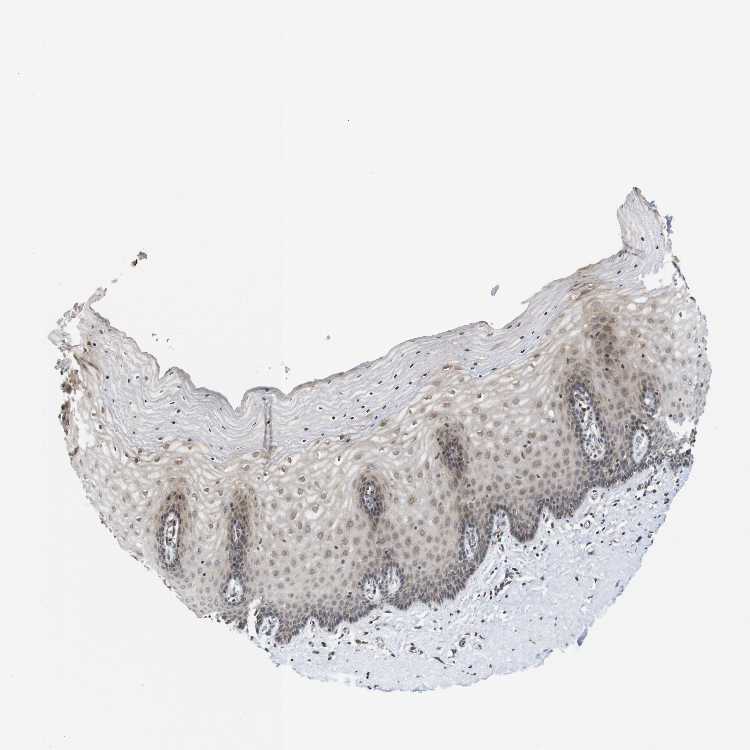

TISSUE PRIMARY DATA CERVIX Show tissue menu

CERVIX - Antibody stainingi

Antibody staining in the annotated cell types in the current human tissue is reported as not detected, low, medium, or high, based on conventional immunohistochemistry profiling in selected tissues. This score is based on the combination of the staining intensity and fraction of stained cells.

Each image is clickable and will lead to virtual microscopy that enables deeper exploration of all samples and also displays staining intensity scores, fraction scores and subcellular localization as well as patient and tissue information for each sample.

Antibody HPA011224Antibody HPA011938

Glandular cells HighHigh

Squamous epithelial cells LowHigh